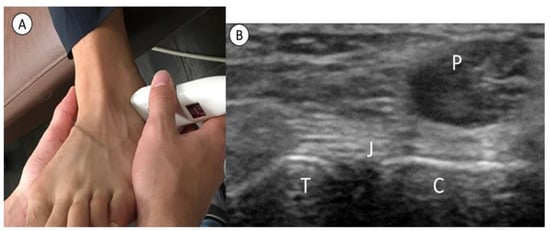

2.2. Procedures